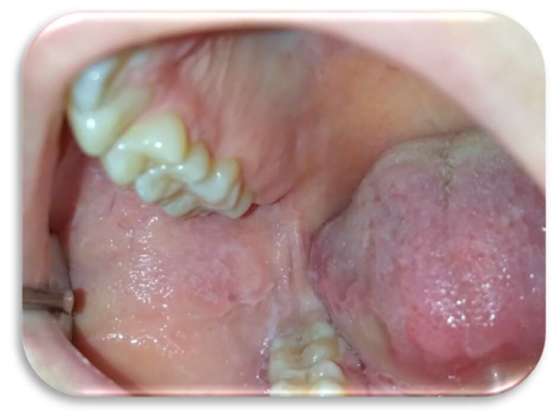

Al quarto giorno di applicazione, la paziente riportava un notevole miglioramento sintomatologico. A sette giorni c’era stata una regressione completa delle lesioni (Figure 5-6), con mucosa integra e normocromatica dove residuava linea alba a livello genieno e linguale (Figure 7-8), per la quale era stato consigliato alla paziente l’uso di un bite inferiore in resina morbida per evitare ulteriori traumi ai tessuti molli.